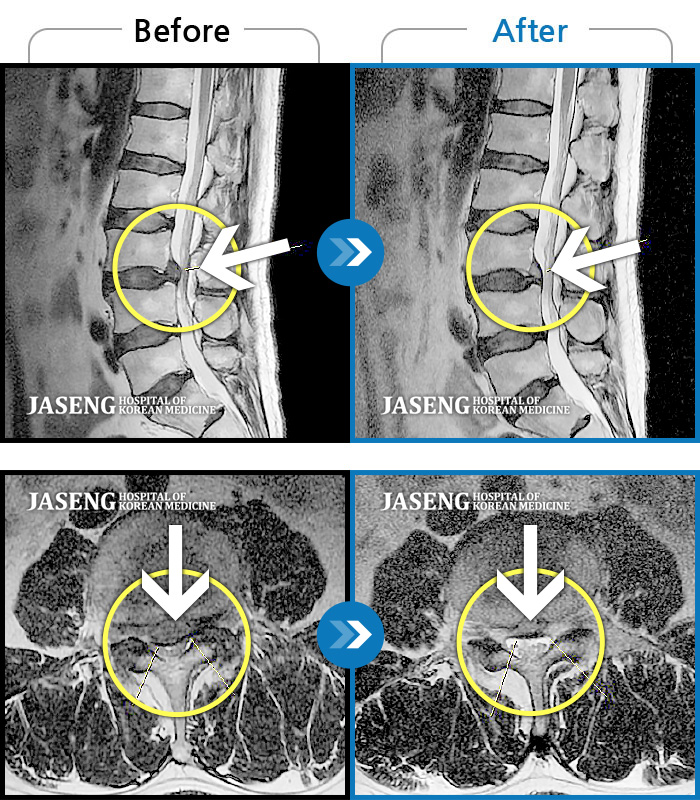

Before

After

환자에게 사전 동의를 받아 동일 조건에서 촬영되었습니다.

개인에 따라 치료 후 부작용이 발생할 수 있으니 의료진과 상담 후 치료를 진행하시기 바랍니다.

허리 통증과 왼쪽 다리 저림이 너무 심해서 걷기도 잠자기도 힘들었어요

허리, 둔부 및 다리로 통증과 저림이 심해서 옆으로 잘 수 없어요.